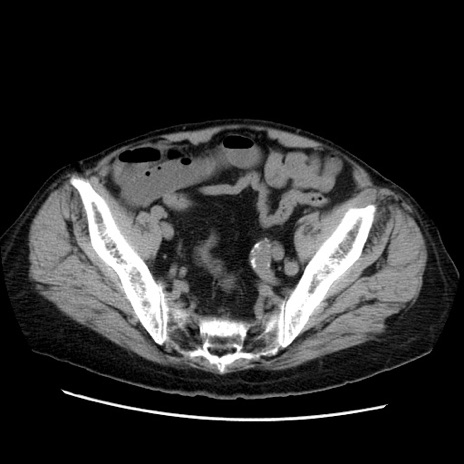

症例21(横断像)

【症例】70歳代男性

【主訴】腹痛

【現病歴】肝硬変・肝細胞癌にてかかりつけの方。約9時間前に食後より腹痛出現。症状が徐々に増悪し、嘔吐出現したため来院。

【既往歴】肝硬変、肝細胞癌(RFA、TACE後)

【身体所見】意識清明、表情苦悶様、BT 36℃、BP 129/78mmHg、P 88bpm、SpO2 97%(RA)、右上腹部から心窩部にかけて圧痛あり、反跳痛なし、筋性防御あり。

【データ】WBC 5800、CRP 0.16